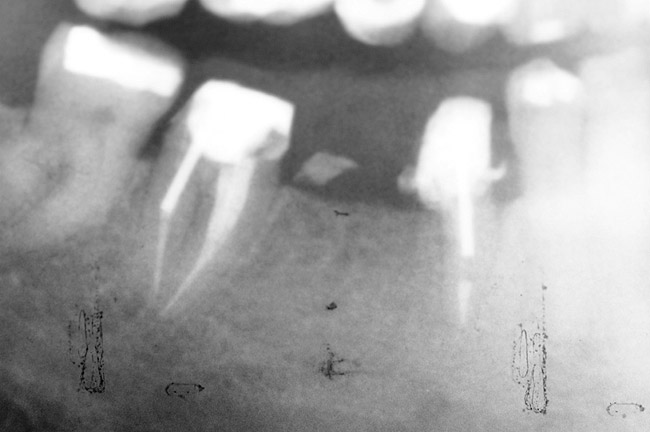

Next, the clinician must consider the teeth’s proximity to critical structures. Figure 16 shows a panoramic radiograph of a patient with advanced periodontal disease. As can be seen in this radiograph, the bone loss around the maxillary molars was very close to the maxillary sinuses and the bone loss of the distal and furcal areas of tooth No. 30 was close to the inferior alveolar nerve. This demonstrates an adverse effect of keeping teeth too long. In this case, the bone height in the area of tooth No. 19, where the tooth had been lost years earlier (and no RPD was worn), was significantly more coronal than in the area of tooth No. 30.

Figure 16  Panoramic radiograph showing generalized advanced bone loss. In the lower left quadrant, teeth Nos. 17 through 20 were lost many years earlier, and the bone level has a significantly more coronal position than the corresponding lower right quadrant where the teeth were retained.